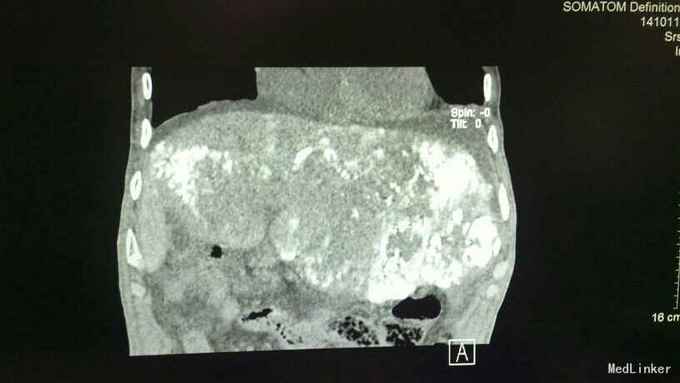

诊断:1、原发性肝细胞癌(巨块型) 2、肝内转移并子灶形成 3、低蛋白血症 4、胸、腹腔积液(少量) 治疗:入院后完善相关常规、生化检查如上述,综合评估病情后考虑患者巨块型肝癌大小约达30*13cm,存在肝癌肿块破裂大出血风险可能性极大,遂立即向其家属告病重。治疗上予护肝、补充白蛋白、护心、补液等对症支持治疗,3日后送手术室行”肝癌血管介入化疗栓塞术(TACE术)“,术中先选取肝动脉,予”氟脲苷+卡铂+平阳霉素+丝裂霉素“向血管行灌注化疗,再予碘化油向血管内灌注以栓塞血管阻断肿瘤血供,再选取肠系膜上动脉,再予上述化疗药物向血管内行灌注化疗。术后患者出现上腹部疼痛、腹胀,食欲严重下降,发热,呈中高热,呕吐数次。均考虑患者介入术后常见不良反应及肝脏及肿块栓塞后液化坏死所致。术后常规予抗感染、护肝、护胃、护心、止呕、补蛋白、适当利尿、维持电解质平衡、加强护理、记24小时尿量等对症支持治疗。病情好转并稳定后复查上腹部CT较入院时缩小,具体见下图所示,提示治疗有效。

随访:随访一月,患者肝左叶巨块型肝癌较前缩小。查体触诊上中腹部可及一肿块大小约24*8cm,于剑突下8cm可触及,于右侧肝肋缘中点下2cm处可触及,质地硬,边缘不规整,表面凹凸不平。 讨论:TACE术:是指将导管选择性或超选择性插入到肿瘤供血靶动脉后,以适当的速度注入适量的栓塞剂,使靶动脉闭塞,引起肿瘤组织的缺血坏死。使用抗癌药物或药物微球进行栓塞可起到化疗性栓塞的作用,称之为TACE。目前最多用于肝癌的治疗,包括: 肝动脉插管化疗栓塞,或肝动脉插管化疗灌注。我们都知道:肿瘤的生长有赖于肿瘤新生血管的形成,当肿瘤生长至一定体积(1~2mm)时,由于缺氧和局部组织PH值的下降,肿瘤便会分泌促血管生成因子,加速肿瘤新生血管的形成,以提供肿瘤生长所需要的氧和营养成分。TACE作为临床治疗肝细胞癌的重要方法,主要通过栓塞肿瘤的供血动脉,阻断肿瘤的血供,导致肿瘤缺血、缺氧,达到抑制肿瘤生长、促使肿瘤细胞坏死、凋亡的目的。适用于原发性或转移性肝癌、肝癌术后复发(肝功能Child分级为A、B-级)、肝血管瘤、肾癌、盆腔肿瘤等的治疗以及鼻咽癌、肺癌、消化道、盆腔肿瘤大出血时的栓塞止血等。 特别是在此例中:患者为73岁高龄的老年患者,又是如此巨块型肝癌,大小约达30*13cm,已经不具备手术指征,因为手术风险性极大,极大可能会因为在术中各种原因导致肝癌破裂而大出血不止却无法抢救,甚至根本抢救不过来!或其他原因记其他不利因素,使得患者及其家属选择保守治疗的。而此时,TACE术就特别适用于这一类患者,既可以收到一定的疗效也可以缓解病情进展,延缓生命,改善生活质量。并且TACE术还可以按照这个原理扩展到其他的肿瘤类型,比如肺癌,直肠癌,妇科恶性肿瘤,胃癌等等,均可以尝试行动脉灌注化疗,亦可以称之为局部化疗。比起全身静脉化疗,此法可以使病灶(肿瘤)更局限更集中吸收化疗药,再辅以差价量化疗会取得不错的效果。